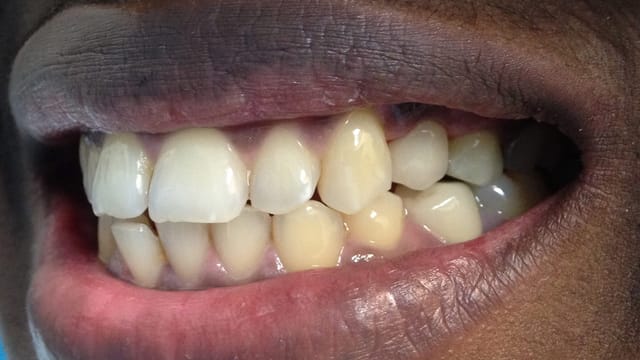

Below is a few examples of what DENTAL IMPLANTS can do for you and your smile!